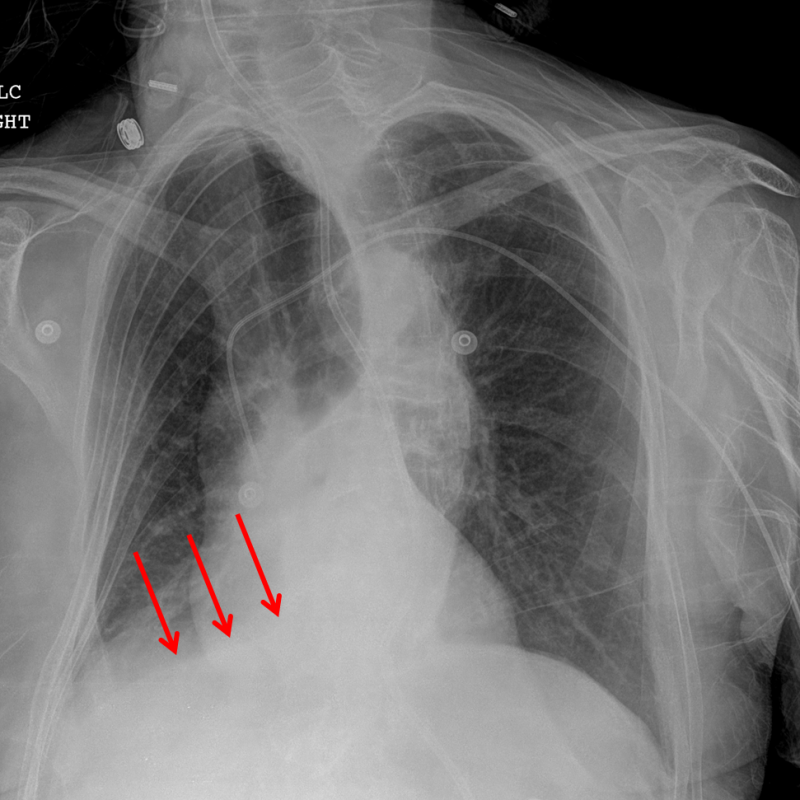

Age: 79

Sex: Female

Indication: Shortness of breath

Sample ReportRight lower lobe collapse with question of right hilar fullness. Recommend chest CT to exclude an obstructing hilar mass. Superimposed aspiration/pneumonia at the right lung base is not excluded, though the right basilar opacification could be entirely explained by lobar collapse.